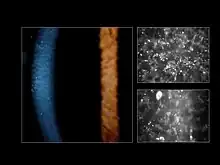

| Appearance of the cornea by slit-lamp biomicroscopy (left image) and by confocal microscopy (right image) (Courtesy Dr. Charles N. McGhee) | |

Fleck corneal dystrophy, also known as Francois-Neetens speckled corneal dystrophy, is a rare form of corneal dystrophy. It is caused by mutations in PIKFYVE gene. Small opacities, some of which resemble "flecks", are scattered in the stroma of the patients. Other opacities look more like snowflakes or clouds. The disease is non-progressive and in most cases asymptomatic, with mild photophobia reported by some patients. In a single case report, a corneal transplantation was performed for concurrent keratoconus, and at 10 years follow-up there was still no evidence of the inclusions in the stroma.[1]